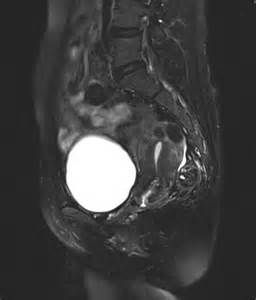

磁共振胰膽管造影(Magnetic Resonance Cholangiopancreatography, MRCP)是利用重T2加權脈衝序列來顯示具有非常長T2弛豫時間組織結構的技術。實質性器官如肝臟、脾臟和胰腺的T2弛豫時間短,在重T2加權序列上表現為低信號。脂肪組織具有中等長度的T2弛豫時間,可通過運用各種脂肪抑制技術(如頻率選擇或反轉抑制)對脂肪信號進行抑制。快速流動的液體如門靜脈或肝靜脈內的血流,由於流空現象在影像上表現為信號缺失,只有靜止或相對靜止的液體表現為高信號。而膽管系統內的膽汁屬於相對靜止的液體,因此MRCP可清晰顯示膽管系統的形態結構。 單層面厚層採集,其特點是不需要進行後處理,獲得的整個膽管系統體積的MRCP投影圖像只有1層,類似於X線的胰膽管造影。該技術採用長TR時間的SSFSE(也稱單次激發的RARE技術),掃描時間極短。利用GE 0.2T,Signa Profile永磁型磁共振成像儀,採用軀體軟性線圈,不用呼吸門控,患者檢查前禁食8~12h,定位前進行屏氣訓練(吸氣―呼氣―屏氣)。操作時先行橫斷T2WI掃描,然後以橫斷圖像顯示的擴張膽管為中心做放射狀定位掃描。MRCP成像參數為:快速自旋迴波序列(FSE),單次激發(Single-shot)成像,TR/TE=18300/910,觀察野38cm,層厚80mm,重建矩陣256×192,單層掃描時間2s。屏氣時間短,患者易配合,圖像質量良好。為了提高解析度及從不同角度觀察病變部位形態特點,我們採用一種新的定位掃描方法:(1)利用薄層定位掃描,提高組織解析度,特別是對擴張不明顯的膽管病變需要進行層厚調整。在完成T2WI掃描後,選擇MRCP序列,首先進行參數調整,進一步定位,層厚減半至40~50mm,以消除容積效應的影響,重建矩陣256×192,單層掃描時間2s。(2)通過任意方位的MRCP序列掃描,豐富MRCP診斷信息。定位方法是經常規MRCP放射狀定位掃描後,在顯示病變的層面上仍以MRCP序列進行任意方位薄層定位掃描,進一步明確病變。(3)運用長間隔激發脈衝進行掃描,可以提高圖像的信噪比。即在手動掃描時,先讓患者憋氣,並按1次scan鍵,出1幅圖像,間隔5~6s後,再一次按下scan鍵,再出1幅圖像,依次在患者憋氣時進行如上操作。經過改進方法,對小的膽總管結石及觀察狹窄部位形態常常要比常規MRCP敏感性高,進一步豐富了MRCP的診斷信息。